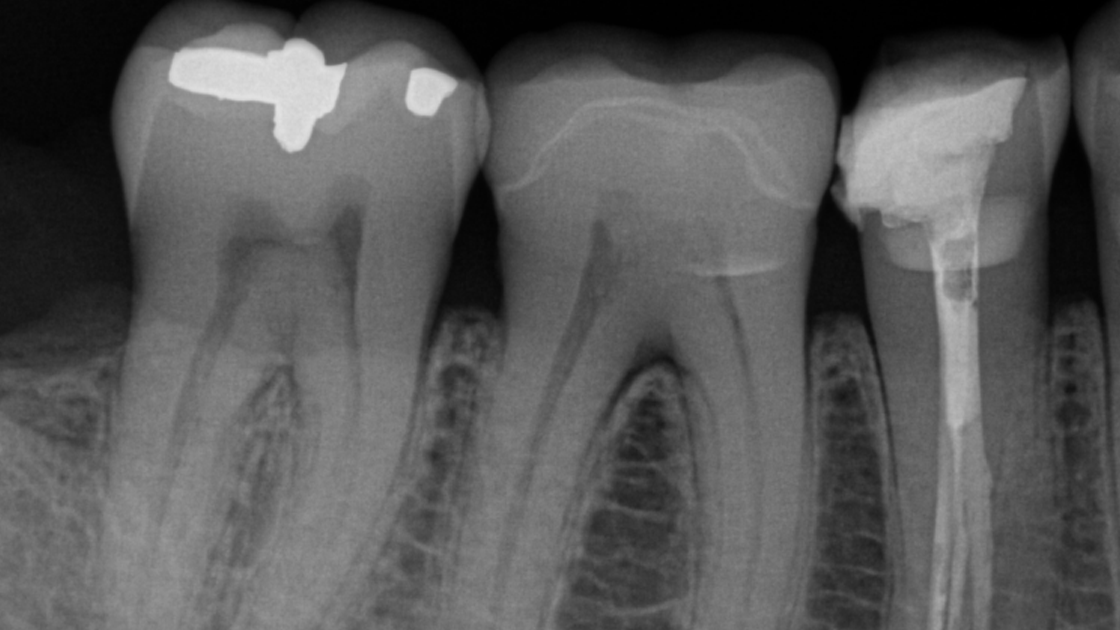

Whether you need intraoral X-rays to assess a symptomatic area or ongoing endodontic treatment, Dentsply Sirona’s intraoral product family has the right solution to support your workflow. The intraoral X-ray portfolio has been engineered to help you reach precision in your X-ray captures, especially when it comes to the positioning of your system. Our intraoral X-ray products are also optimized for easy integration and streamlined workflows, thanks to a state-of-the-art digitalization and seamless workflow automation. Thanks to their connection to Sidexis 4 and DS Core, the solutions allow you to enter the Dentsply Sirona digital universe and harness all the benefits of this evolving platform.